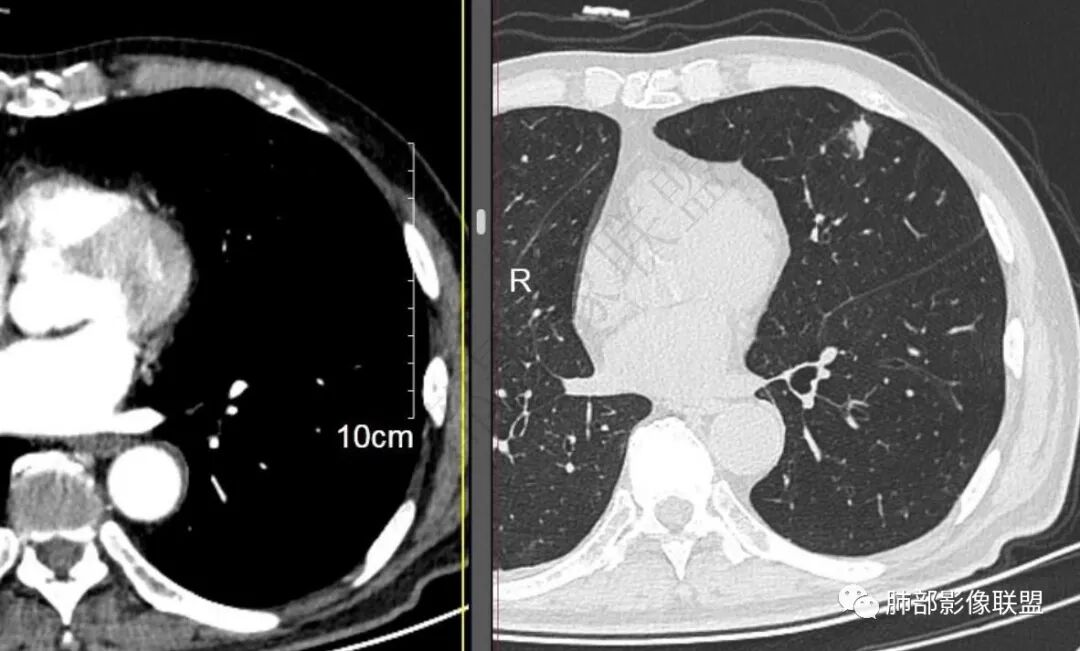

二..发现左肺上叶舌段实性密度小结节影,不规则略呈半环形,边界清楚,未见分叶、毛刺及磨玻璃晕。未见卫星病灶。

9个月后病灶明显增大,边缘较平直,部分膨隆,锁扣样外观,仍旧缺乏典型深分叶及张力,未见胸膜凹陷。

再1个多月后病灶继续增大,较明显不均匀强化,肺门一侧见低密度区。病灶边缘相对不清,可见毛刺。